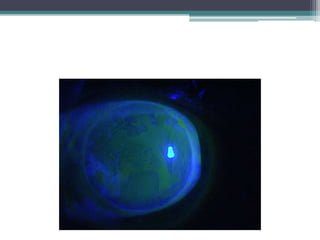

Stem cell deficiency

• 65 Y.O man with a history of alkaline burn.

• Presented initially 5 years ago with a melted,

perforated cornea.

• Underwent PK, achieved 20/30 was stable until

1 month ago. Presented with visual acuity of

20/200, partial stem cell failure

• Underwent selective epithelial debridment with

prokera, achieved 20/70 and improving.

• Avoided a stem cell transplant